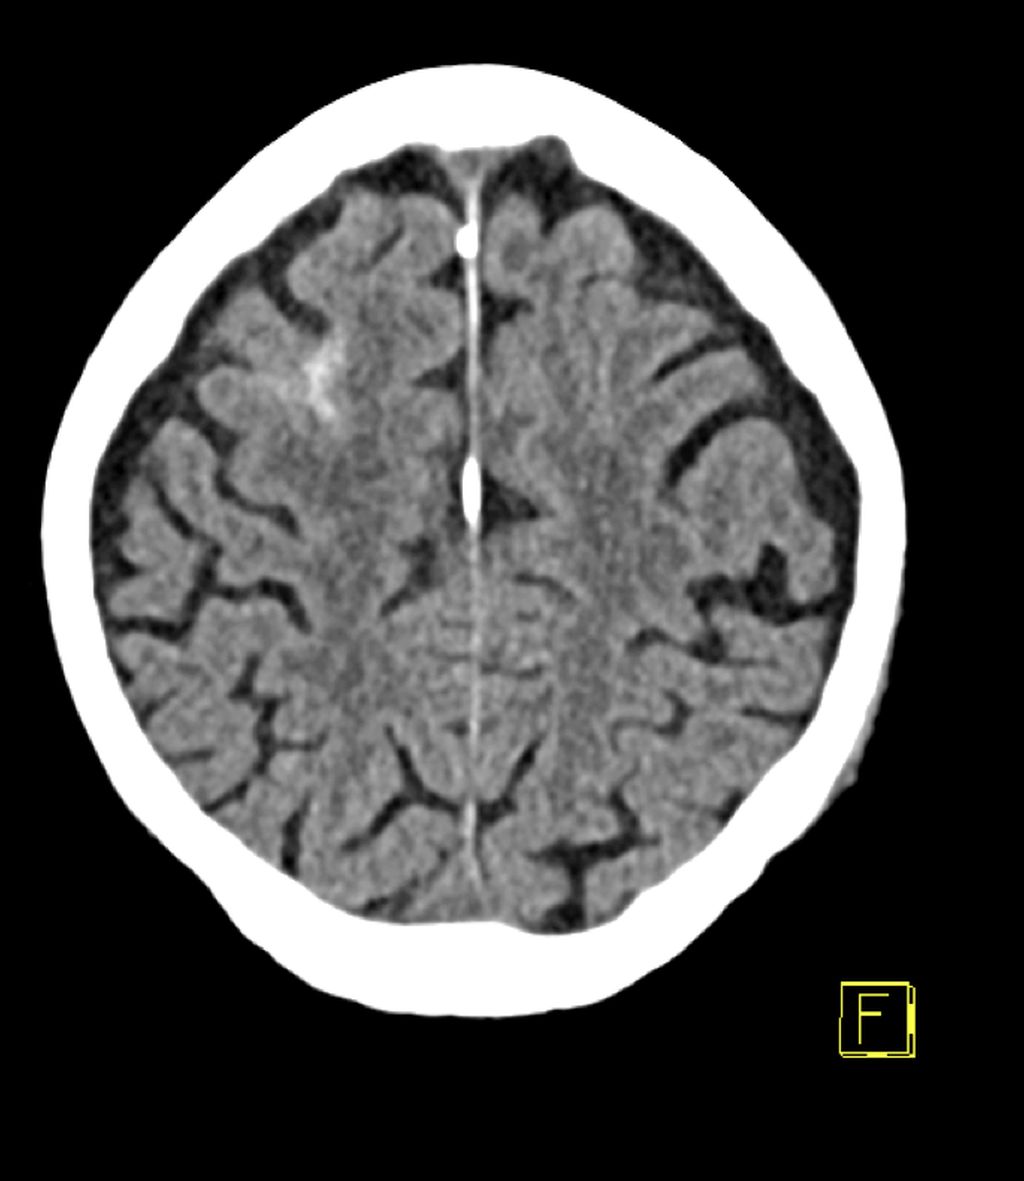

Abb. 1: 88-jähriger männlicher Patient erleidet unter der Einnahme von Rivaroxaban (Xarelto®) im Rahmen eines häuslichen Sturzes eine Subarachnoidalblutung rechts frontal

Dieser epidemiologische Hintergrund spiegelt sich im klinischen Alltag wider. Die Behandlung von Patient*innen mit leichtem SHT unter laufender oraler Antikoagulation ist eine alltägliche Situation für jede Traumatologin und jeden Traumatologen in der Notfallambulanz. Die intrakranielle Hämorrhagie stellt dabei eine gefürchtete Folge dar (Abb.1). Das erhöhte Risiko für intrakranielle Blutungen bei Vitamin-K-Antagonisten (VKA) wurde bereits vor Langem nachgewiesen, durch die Einführung der direkten oralen Antikoagulanzien (DOAK) geraten die VKA jedoch immer mehr in den Hintergrund.4,5